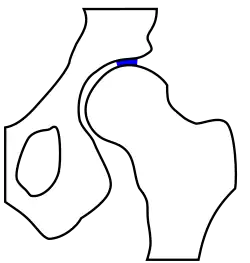

unten: gesundes Hüftgelenk

Das Röntgenbild kann auch Auskunft über präarthrotische Deformitäten, beispielsweise bei einer Hüftdysplasie (vgl. Abb.) als Ursache der Coxarthrose geben.[18] Hier ist der Hüftkopf nicht ausreichend überdacht und steht deswegen dezentriert nach oben / seitlich heraus. Dadurch resultiert eine Verkürzung der Beinlänge. Im Laufe der Zeit kommt es zu einer massiven „Entrundung“ des Hüftkopfes, der Gelenkspalt ist fast ganz aufgehoben, das Hüftgelenk wird steif.